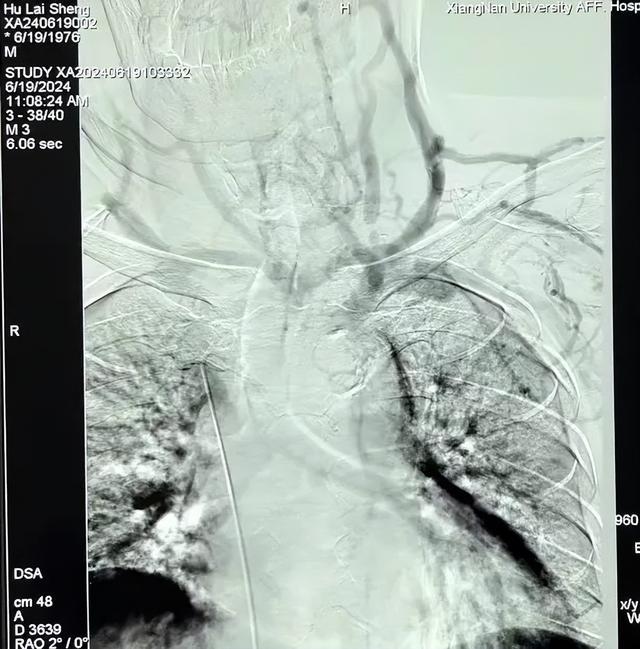

(▲术中造影显示左侧头臂静脉闭塞)

术中,手术团队经左上肢动静脉内瘘血管及股静脉穿刺,置入导管鞘,经造影导管造影再次证实左侧头臂静脉闭塞,使用球囊导管预扩张后,将支架植入病变部位,复查造影显示中心静脉通畅,手术过程顺利,困扰患者多时的难题终于解决了。